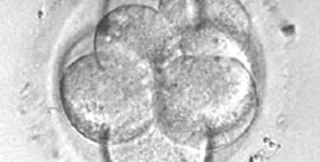

Австралийское правительство выдало первую в мире лицензию на клонирование человека.

Как передает радио "Маяк", лицензию получила фирма Sydney IVF, которая специализируется на экстракорпоральном оплодотворении.

Документ дает право клонировать эмбрионы людей для производства стволовых клеток.